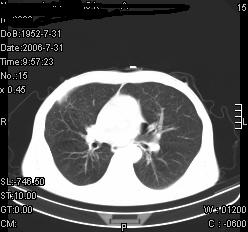

患者,男,54岁,咳嗦,咳痰20天。抗炎治疗2周。现esr76mm/h,目前患者症状明显好转,但发现两次ct片未见明显变化。两次分别做与7.25、7.31。第一次诊断右肺上叶炎症累计胸膜。大家看,从影像上内排除结核吗?

结核的可能性非常大,右上肺病变应该考虑干酪性肺炎。理由:

1.纵隔内多发淋巴结肿大。

2.esr76mm/h。

3.虽经抗炎治疗肺窗病灶有所吸收、减小,但纵隔窗病灶形态、密度、范围无明显变化。如果是单纯的大叶性肺炎,“抗炎治疗2周,目前患者症状明显好转”病灶应该基本消散了,至少也处于吸收消散期,密度变淡、范围变小。同时本病例所示其内的密度不均匀,见多发大小不一空洞样影也不符合大叶性肺炎吸收消散期表现。

病灶特点:片状 索条 结节混杂影,部分融合,密度不均,广泛累及相应胸膜.

临床治疗;二周未吸收.但症状好转.

多考虑:肺结核.